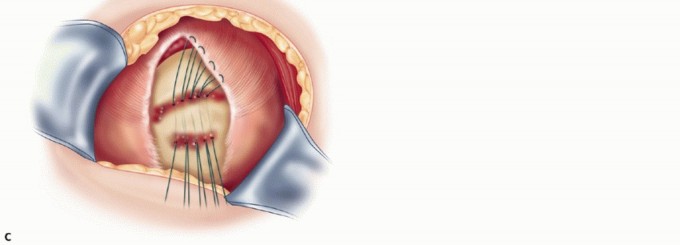

TECH FIG 4 • A. Intraoperative photograph showing freshened edges of tear. Healthy tendon is seen but not bleeding edges. Note cancellous trough at the anatomic neck and the greater tuberosity. B. Triangular tear with apex medially. C. Drawing of sutures passed through bone tunnels in the trough and greater tuberosity, pulling the edge of the cuff into the trough. Anchors can be used instead. D. Completed L-shaped repair. (D: From Neviaser R, Neviaser AS. Open repair of massive rotator cuff tears: tissue mobilization techniques. In: Zuckerman J, ed. Advanced Reconstruction: Shoulder. Chicago: American Academy of Orthopaedic Surgery, 2007:177-184.)

When the leading edge of the cuff can be brought to its insertion on the greater tuberosity, a shallow trough is made in the anatomic neck at the greater tuberosity ( TECH FIG 4A ).

Drill holes are made in the trough and the lateral side of the tuberosity and connected with a punch. Locking horizontal mattress sutures or modified Mason-Allen sutures are placed in the cuff and passed through the bone tunnels created by connecting the drill holes ( TECH FIG 4C ). Suture anchors can also be used in the trough and the tuberosity in a double-row fashion instead of the bone tunnels.

With the arm in some internal rotation and slight abduction, the sutures are tied securely to bring the free edge of the cuff into the trough.

This leaves a longitudinal split, which is sutured side to side, not only closing the split but also helping to relieve tension on the cuff advanced into the trough ( TECH FIG 4D ). -